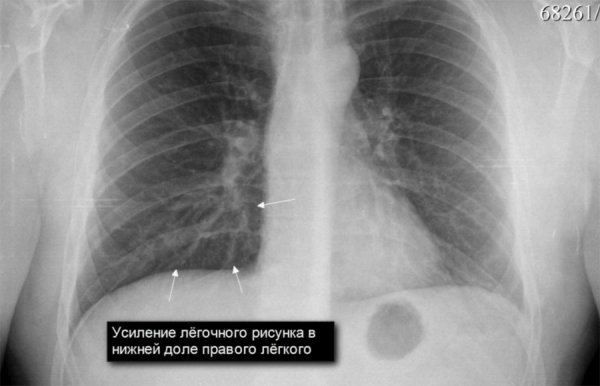

Усиление легочного рисунка